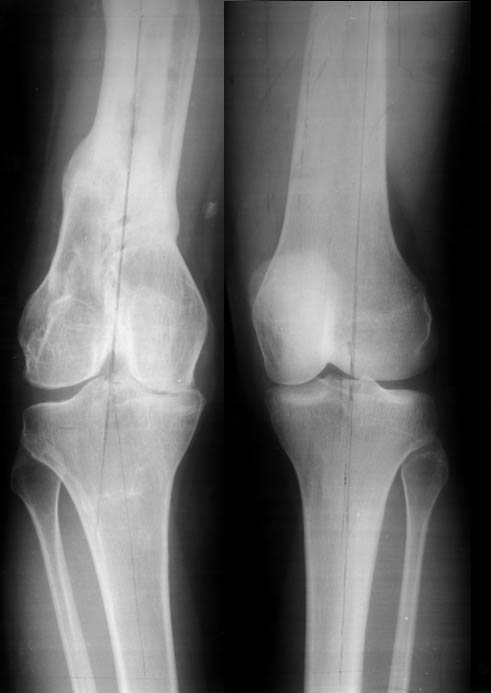

Женщина, 29 лет. В 2001 году получила политравму (таз, открытый многооскольчатый перелом правой бедренной кости на границе средней и нижней трети со смещением,

открытый перелом правой голени, пятки, закрытый - правого надколенника, поперечного отростка L4, пальцев кисти, сотрясение головного мозга).

Переломы конечностей лечились АВФ. В настоящее время стойкая разгибательная контрактура правого коленного сустава (сгибание 105-110 гр., разгибание 160-165 гр.), варусная деформация, болевой синдром.

Вопросы: 1.Определение уровня корригирующей остеотомии для устранения варусной деформации правой нижней конечности (остеотомия на бедре или голени)?

2. Рекомендации по оперативному пособию для устранения посттравматической варусной деформации правой нижней конечности?